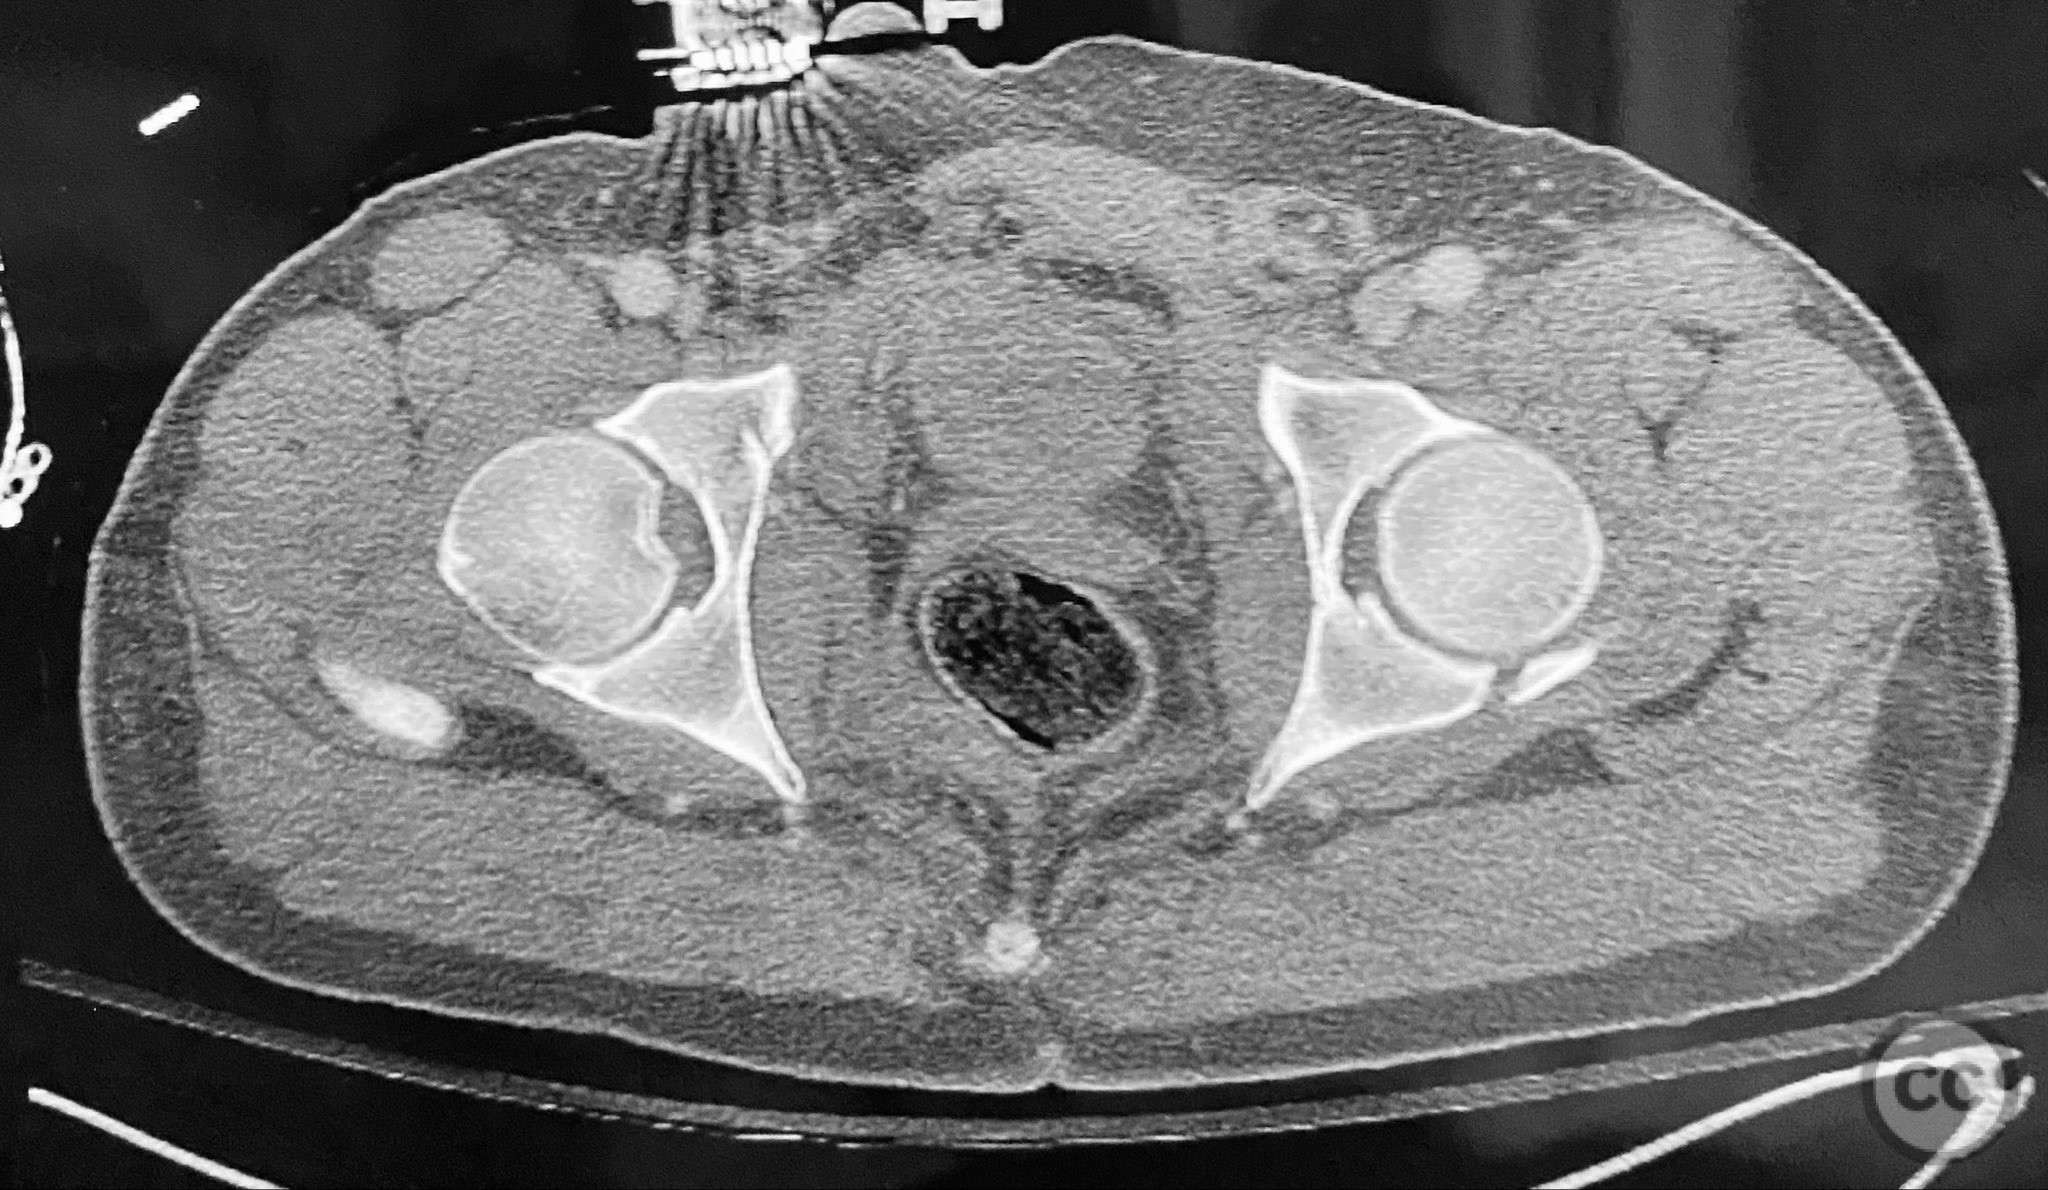

Clinical and radiological findings:  Adult male with a closed, comminuted left femoral shaft fracture and complex pelvic ring injury. Initial imaging demonstrated bilateral sacroiliac (SI) joint disruptions and a left-sided transtectal transverse acetabular fracture (Letournel-Judet: transverse type), with the fracture line exiting through the posterior wall region but without a discrete posterior wall fragment. The femoral head was displaced caudally, following the unstable distal acetabular segment, resulting in loss of congruency with the intact acetabular dome. There was also a symphyseal disruption. No associated abdominal, visceral, thoracic, cranial, or other injuries were present. Application of a circumferential pelvic binder resulted in visible changes in pelvic alignment on imaging. AO/OTA Classification: - Pelvic ring: 61-C1.3 (bilateral SI joint disruption, complete instability) - Acetabulum: 62-B1 (transverse fracture) - Femur: 32-C3 (comminuted diaphyseal fracture)